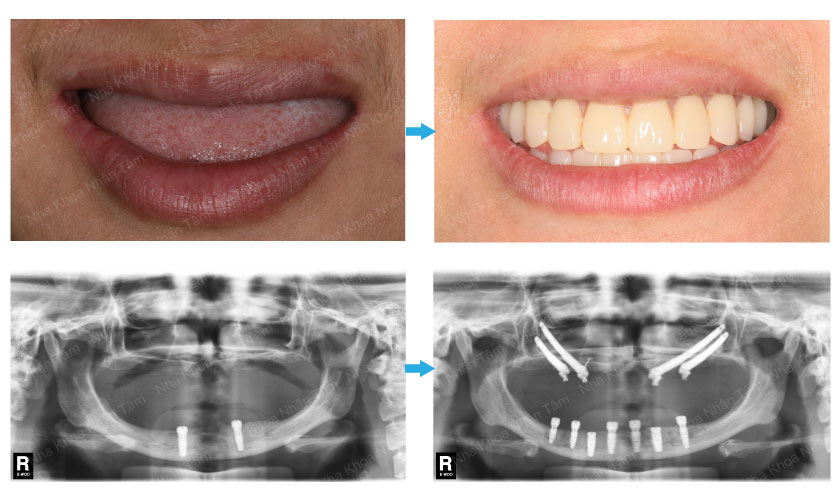

Đây là ca cấy ghép răng cho người thiếu bẩm sinh (*) được thực hiện thành công ngày 3/6/2016 do Tiến sĩ bác sĩ Võ Văn Nhân cùng ê-kíp.

Ca phẫu thuật cấy ghép răng cho người thiếu bẩm sinh được thực hiện song hành hai kỹ thuật phức tạp dời dây thần kinh hàm dưới (*) và cấy ghép implant xương gò má (*) để phục hồi toàn bộ răng hàm trên và hàm dưới cho bệnh nhân. Sự thành công này đánh dấu một bước tiến mới trong ngành implant nha khoa Việt Nam.

Cấy ghép implant cho người bị thiếu răng bẩm sinh (*), đây là ca phẫu thuật phức tạp này được thực hiện cho Bệnh nhân Nguyễn Thị Kim Huệ (30 tuổi – Hà Nội) bị thiếu răng bẩm sinh (không có răng từ khi mới sinh) nên xương hàm không phát triển.

Bên cạnh đó, Bệnh nhân phải đeo hàm răng giả từ khi 14 tuổi. Do vậy, đến nay xương hàm trên và hàm dưới bị tiêu trầm trọng đến nổi mà các kỹ thuật nha khoa truyền thống không thực hiện được.

Sau 4 tiếng làm việc tập trung cao độ, Tiến sĩ. Bác sĩ Võ Văn Nhân và ê-kíp đã thực hiện thành công ca phẫu thuật.

Theo đánh giá ban đầu, hiện tại tình trạng sức khỏe của bệnh nhân đã hồi phục, tiếp xúc tốt và đã xuất viện viện vào ngày 4/6. Dự kiến 1 tuần sau phẫu thuật để giảm sưng và phù nề, bệnh nhân sẽ được gắn răng cố định trên implant.